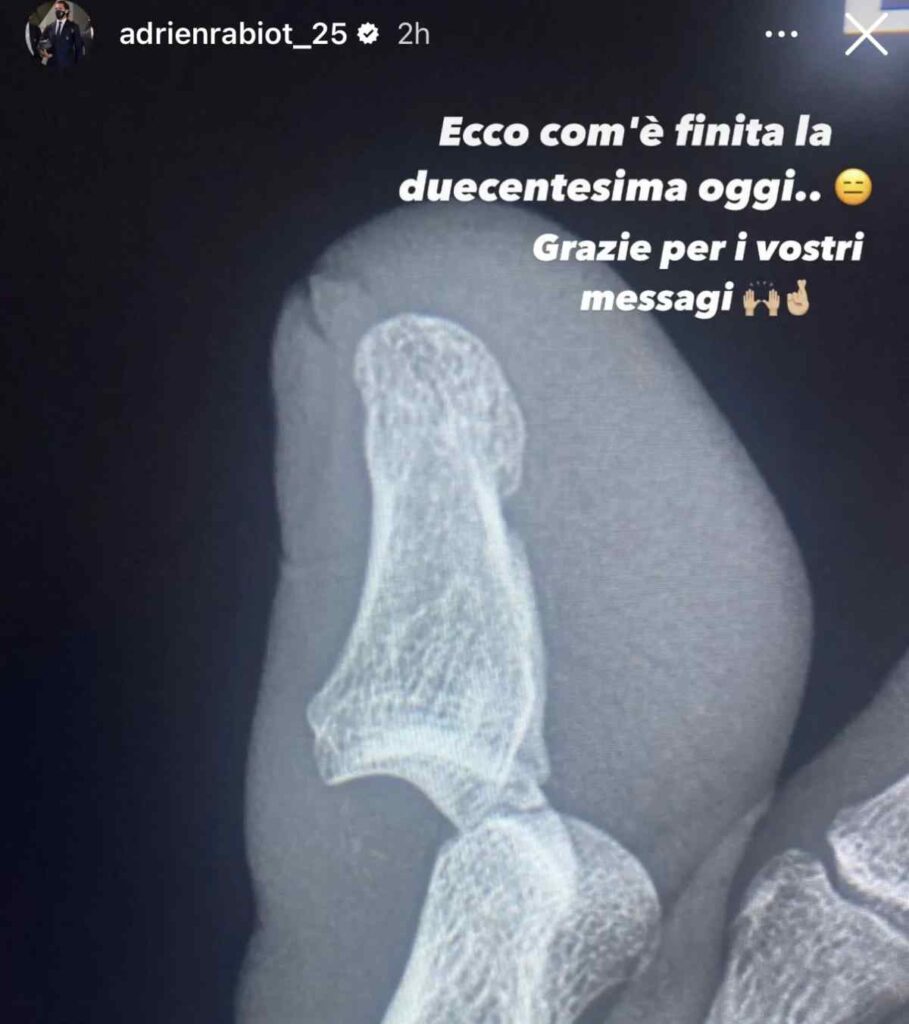

Dopo poche ore dalla gara, Adrien Rabiot ha tenuto ad aggiornare tutti sullo stato delle sue condizioni fisiche con una Instagram stories, l’immagine ha scioccato i supporter bianconeri. Il centrocampista francese, alla sua 200esima presenza con la Juventus, è stato costretto a lasciare il terreno di gioco dopo appena 29 minuti. A margine della sfida contro il Frosinone, mister Massimiliano Allegri ha dovuto rinunciare a Rabiot in seguito ad uno scontro di gioco con Gleison Bremer. Sugli sviluppi di un corner, il difensore brasiliano ha rifilato a Rabiot un pestone al piede sinistro.

Dopo l’infortunio al piede sinistro, la società bianconera ha sottoposto il centrocampista ad esami dettagliati per capire la chiara entità dell’infortunio. Adrien Rabiot ha voluto fare luce su quanto accadutogli, svelando l’esito della radiografia al piede sinistro.

Il centrocampista, che ha lasciato il terreno di gioco dolorante, ha rimediato una lussazione falange al primo dito del piede destro. I tempi di recupero sono ancora da valutare. In serata, Adrien Rabiot ha voluto aggiornare tutti sulle sue condizioni tramite il proprio profilo Instagram. Il calciatore della Juventus ha postato un’immagine impressionante della lastra al piede, alla quale ha allegato un messaggio: “Ecco com’è finita la 200esima di oggi… Grazie per i vostri messaggi”.